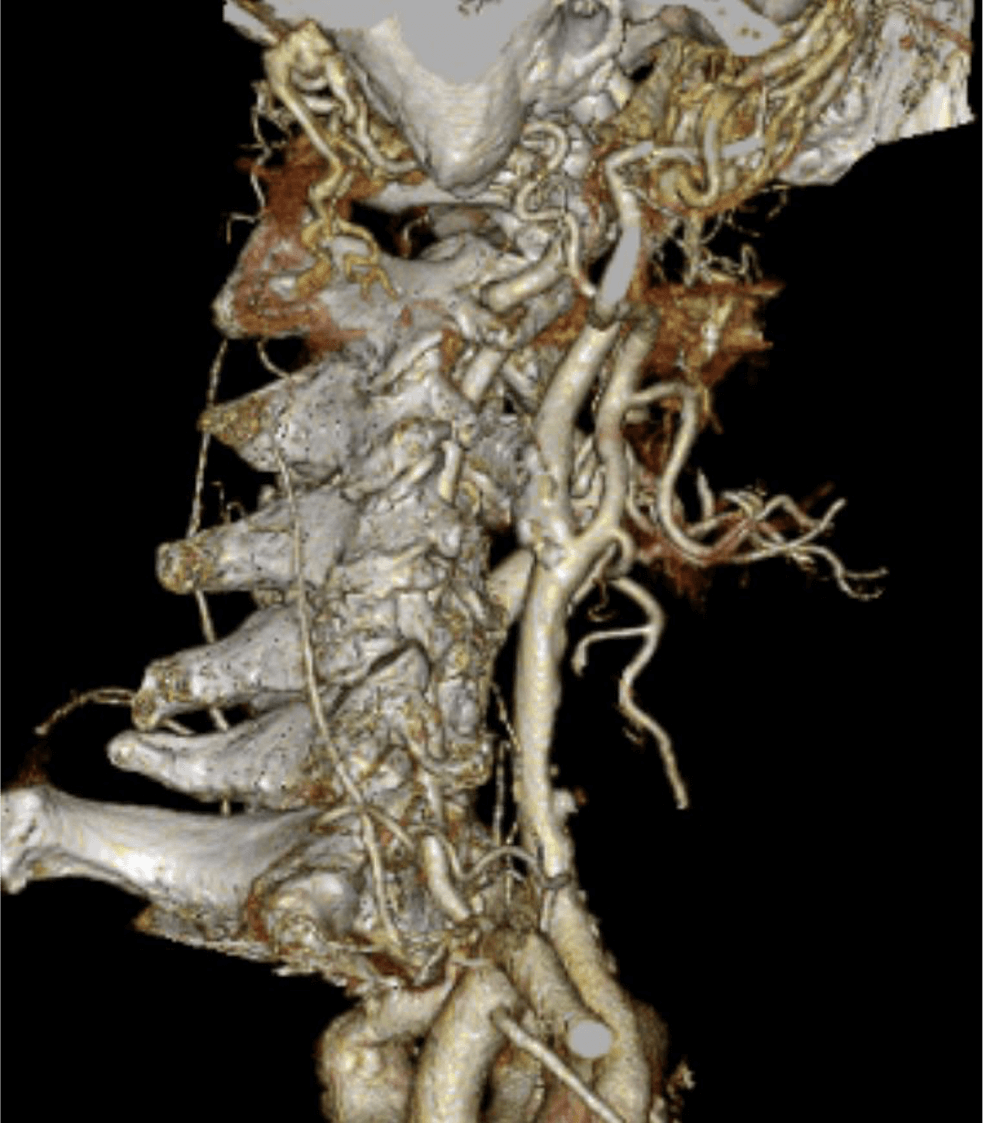

70歳代、男性、52kg、内頸動脈狭窄

右内頸動脈狭窄症の術前評価

2年前に左内頸動脈狭窄症に対して内膜剥離術施行後。今回、右内頸動脈狭窄の進行が疑われ、術前精査のためCT angiography施行。

内頸動脈狭窄症において、造影CTはMRIと並んで必須の検査である。MRIが苦手とする石灰化の評価、薄いスライス厚での狭窄率評価が、造影CTでは行いやすい。動脈相での評価が望ましく、血管内と血管外の境界が可能な限りシャープである方が、狭窄率の評価が行いやすい。

CT技術や撮像プロトコル設定について

Virtual Monoenergetic Imageで高エネルギー側の表示をすることで、金属アーチファクトを低減できたり、今回の症例のように、Iodine mapを用いることでヨード濃度を推定することができたり、Purelumen画像でCaなどの石灰化を除去することで、内腔の表示をより明瞭化する技術がある。シャープネスの高い動脈相の画像が望ましく、ヨード量は600mgI/kgは維持できるように気をつけている。